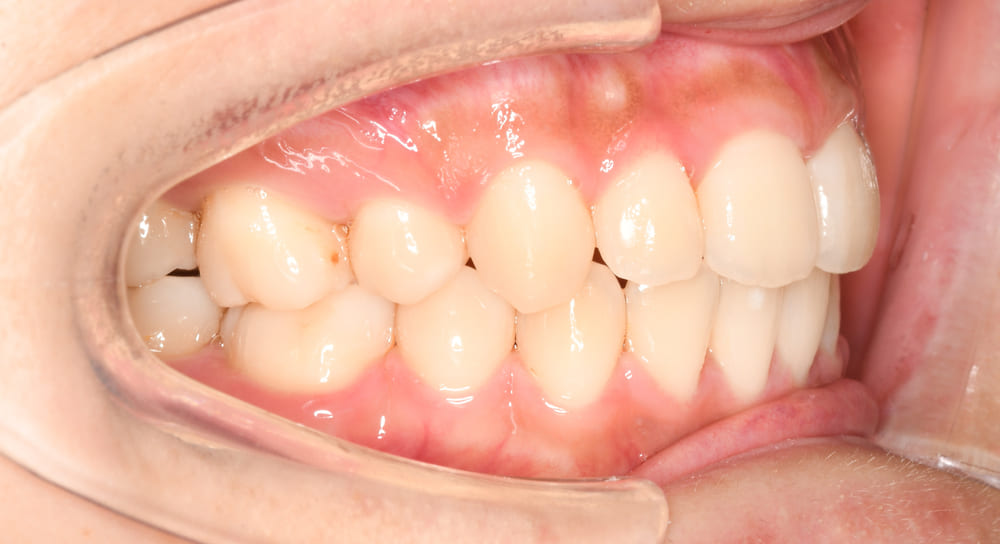

右側からの口腔内写真です。上下顎の前歯が著しく前方に傾斜していることがお分かりいただけると思います。

右側です。上下顎前歯の唇側傾斜が改善され理想的な歯軸傾斜と上下的なかみ合わせを獲得することができました。